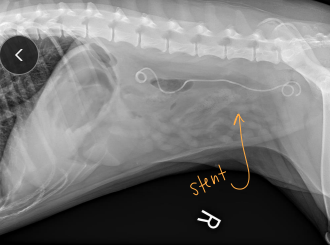

Ureteral Surgical Procedures

Ureteral stent: for dogs w/ obstruction

Ureteral Obstruction

Et: partial (stone, stricture), complete (stone, trauma, ligation, transection)

Cs: lethargy, anorexia, hydronephrosis, azotemia

urination possible unless bilateral

Dt: Rads + contrast, US

Tx: SUB (C), Ureteral stent (D)